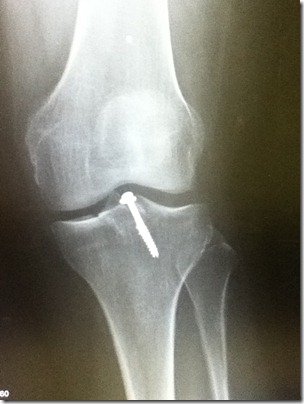

I saw the Dr. again this past Friday… hard to believe it’s been 2 weeks already. I had to get a couple new x-rays…

It’s interesting that this view (from the front) almost perfectly lines up the 2 screws they put in. In my last post I thought the second screw came in from the side because you could only see a portion of it. But I can see now that the second screw is a partial and is used as an anchor to hold the broken off piece of bone in place. They are both inserted at the same angle.